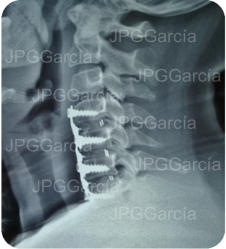

Extrusión discal cervical y tratamiento microquirúrgico

con colocación de cajas intersomáticas

Tratamiento neuroquirúrgico con colocación de cajas intersomáticas

cervicales hasta 3 niveles por vía anterior vistas anteroposterior y lateral

Tratamiento neuroquirúrgico

con colocación de cajas

intersomáticas cervicales hasta

3 niveles por vía anterior vistas

anteroposterior y lateral